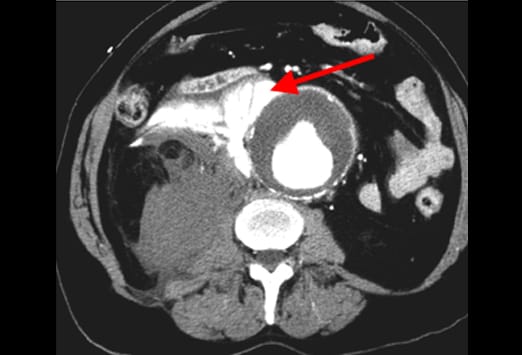

Intravenöses Kontrastmittel (siehe Abbildung) ist ein wichtiges diagnostisches Hilfsmittel. Dieser Patient präsentierte sich mit einer Hypotonie und einer gram-negativen Sepsis, allerdings ohne abdominelle Schmerzen in der klinischen Untersuchung. Das Bild auf der linken Seite, welches mit oralem, aber ohne intravenöses Kontrastmittel durchgeführt wurde, ergab keinen schlüssigen Befund. Das Bild auf der rechen Seite zeigt die erneute Untersuchung nach Gabe von intravenösem Kontrastmittel. Dieses stellt eine verdickte, vermehrt kontrastierte Appendixwand und entzündliche Veränderungen des umgebenden Fettgewebes dar.